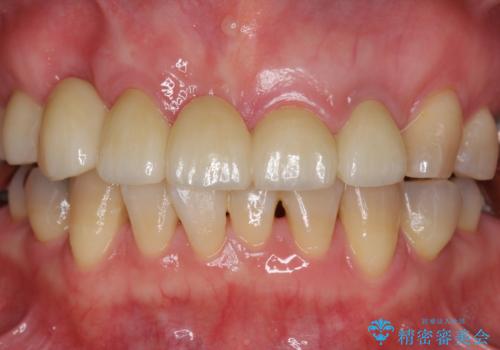

過度な咬合力 歯ぎしりで抜けた歯の欠損補綴

- 前歯を噛みしめにより失い、さらに犬歯もグラグラになり全く噛めなくなり改善を求めて来院されました。

過度な力がかかり周囲の骨に高度な吸収が見られた犬歯は抜歯し、機能・審美性の回復をより咬合力に対して抵抗力のあるブリッジ補綴にて対応します。

ブリッジによる欠損補綴を行ったのち、ナイトガードを夜間装着していただき歯を守ります。